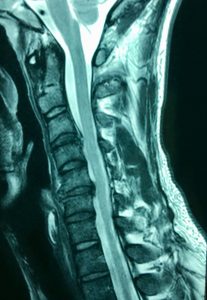

They continued by stating that if they had not met me they'd be lost and hopeless thinking nothing happened to his neck when he was suddenly kicked in the head during martial arts. This caused an obvious damage of at least two discs clearly shown on MRI. See image below.

An irresponsible neurologist ignored it as a cause of any of the myriad symptoms and syndromes he had developed.

This unfortunate male in his 3rd decade was kicked in the head in a sporting match.

The scan delineates extensive disc damage and his symptoms were clearly associated with all sorts of debilitating sympathetic effects and neurological symptoms which were starting to extend deeply into behavioural patterns. His life had become almost unliveable.

One of the doctors he saw was a specialist neurologist who advised that it was normal ageing.

"NORMAL AGEING"?

This stuff infuriates me. For one, degenerative discs at the high level are rare, and the traumatic history described the site of injury satisfactorily. Also, athletic, healthy men in their 20s do not suddenly think suicidal thoughts the month after being knocked unconscious and having to deal with constant pain.